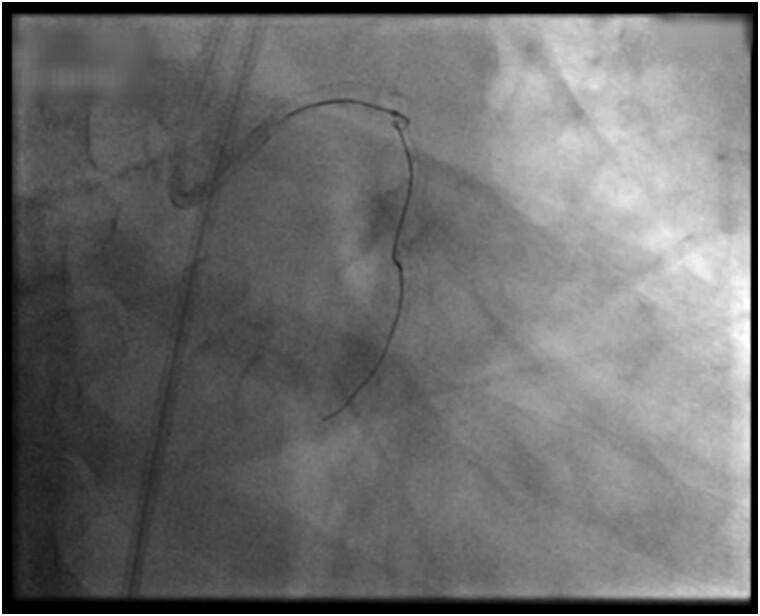

A 52-year-old male patient with diabetes and dyslipidaemia presented with posterior wall myocardial infarction. An angiogram revealed occlusion in the left circumflex (LCX) artery. Attempts to pass a guidewire through the lesion led to its entrapment and eventual fracture. Several techniques and manoeuvres failed to retrieve the fractured guidewire, which remained lodged in the LCX. An endovascular snare catheter also proved unsuccessful. The fragment was eventually removed using the triple-wire technique, although this caused coronary perforation and dissection. The perforation was identified and stented. A subsequent stent addressed a dissection in the left main/left ascending artery area, likely caused by the coronary snare. These interventions were crucial in stabilizing the patient's condition, leading to recovery with a left ventricular ejection fraction of 50% and a viable LCX artery. The patient exhibited an uneventful progression at the 1-year follow-up.

一名52岁男性患者,患有糖尿病和血脂异常,出现后壁心肌梗死。血管造影显示左旋支(LCX)动脉闭塞。试图使导丝穿过病变部位导致导丝陷入并最终断裂。多种技术和操作未能取出断裂的导丝,其仍留在LCX中。血管内圈套导管也未成功。最终采用三线技术取出了碎片,尽管这导致了冠状动脉穿孔和夹层。穿孔被识别并置入了支架。随后的支架处理了左主干/左前降支动脉区域的夹层,可能是由冠状动脉圈套器所致。这些干预措施对稳定患者病情至关重要,患者得以康复,左心室射血分数为50%,LCX动脉存活。患者在1年随访中病情进展顺利。